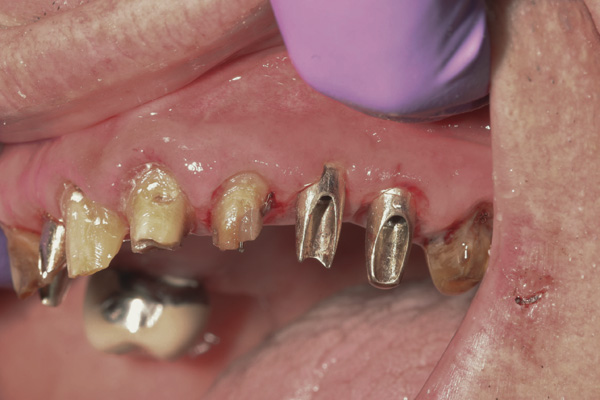

Results: A decision was made to re-prepare all of the abutments intraorally (Figure 3) so that all abutment margins would be at or below the gingival margin. (Of note, tooth Nos. 8 and 9, also shown in Figure 3, were later submerged for the case to be fully implant-supported.) While re-preparation greatly improved the esthetics of the final result, it required retraction cord placement, new impressions, and new castings.

Figure 3 Abutments re-prepared intraorally.

Figure 3

Figure 4 Following osseointegration of an implant at No. 12, recession was observed at the fixture-level impression stage of No. 13; it was decided to re-prepare the margins of the CAD/CAM custom abutment of implant No. 12. Retraction cord was placed prior to preparation to avoid tissue injury and improve visibility of both tooth No. 11 and the implant custom abutment margin. As expected, recession was greater along the distal side of abutment No. 12, adjacent to the healed extraction/newer implant site.

Figure 4